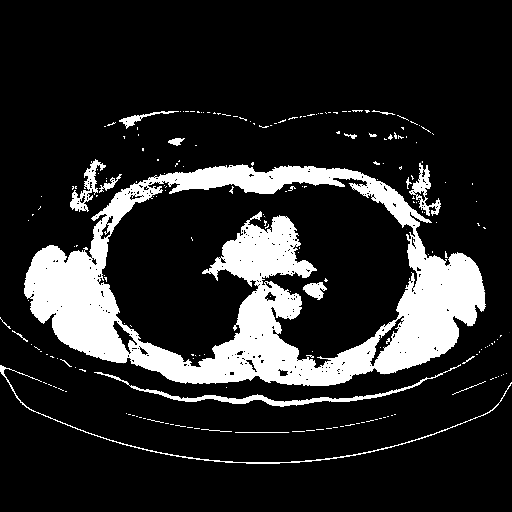

Image Grid

4Γ—3 grid: Rows show different image types (Original NATIVE, Reconstructed NATIVE, Original VENOUS, Generated VENOUS), Columns show windowing techniques (No Window, Lung Window, Mediastinum Window)

Reconstructed NATIVE CT scan (cycle consistency)

Lung window (WL -600, WW 1500 β†’ Low βˆ’1350, High +150)

Actual HU range: [-1350.0, 150.0]

Original VENOUS CT scan

Generated VENOUS CT scan (A→B translation)